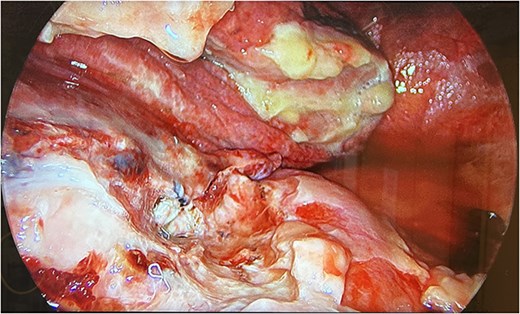

Therefore, the patient was consented for a washout of the chest, and this was conducted on Day 3 from the original procedure. Upon establishing access, it was clear that the collection depicted on the CT thorax was not hemorrhagic but mucopurulent fluid in the presence of an empyema (Fig. 3). Due to the mucopurulent fluid and presence of early-stage organisation of septations and loculated fluid, the empyema was fibro purulent. In line with the European Association for Cardio-Thoracic Surgery (EACTS) consensus and British Thoracic Society (BTS) guidelines for the management of pleural disease, the empyema was graded as stage 2 [4–6].

UVATS camera image depicting fibrin tissue formation of early stage empyema within the hilar and azygos region.

Decortication of the fibrin depositions on the parietal and visceral pleura was carried out with samples taken for microbiology. The patient was irrigated with saline wash and two drains inserted into the apical and basal regions.